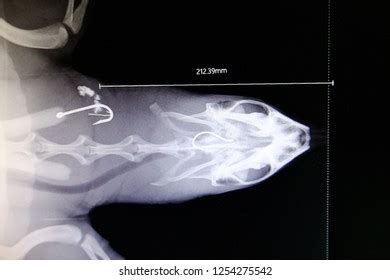

For the dorsoventral (DV) view, the turtle is placed on its back , with the beam entering through the dorsal (top) surface and exiting through the ventral (bottom) surface. The goal is to get a clear, symmetrical image of the turtle’s internal organs and skeletal structures. Start by gently positioning the turtle in dorsal recumbency, ensuring that the spine is straight and aligned with the center of the X-ray beam. Use foam wedges or sandbags to support the turtle and prevent it from rolling. Take care to avoid excessive pressure on the turtle’s limbs or neck. Collimate the beam to include the entire shell and ensure that the central ray is centered over the mid-carapace. This view is particularly useful for assessing lung fields, liver size, and the presence of any abdominal masses or foreign bodies.

The craniocaudal view is less commonly used but can be helpful in certain situations, particularly when evaluating the turtle’s head and neck. The turtle is positioned with its head facing the X-ray tube, and the beam is directed from the cranial (head) end to the caudal (tail) end. This view can be challenging to obtain, as turtles tend to retract their heads into their shells. Gentle traction on the head and neck may be necessary to achieve adequate visualization. Use positioning aids to stabilize the turtle’s head and neck, and collimate the beam to include the area of interest. This view is useful for assessing skull fractures, cervical spine abnormalities, and foreign bodies in the esophagus.